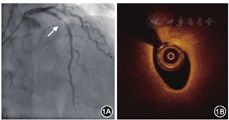

2015年5月11日行冠状动脉造影检查,结果显示:左主干正常;左前降支近段狭窄程度为95%,中远段狭窄程度为30%,血流心肌梗死溶栓试验(thrombolysis in myocardial infarction,TIMI)分级为2~3级;左回旋支远段狭窄程度为70%;右冠状动脉近远段狭窄程度为20%~30%,血流TIMI分级为3级(图1A)。因左前降支近段病变严重,先行球囊预扩张,然后行光学相干断层成像(optical coherence tomography,OCT)检查。OCT结果示最小管腔面积为2.57 mm2,斑块负荷为85.3%(图1B)。以非顺应性高压球囊再次预扩张后,经导丝推送3.5 mm×24 mm NeoVas生物可吸收支架[乐普(北京)医疗器械公司]至左前降支近段病变处,以12 atm(1 atm=101.325 kPa)释放支架。以非顺应性高压球囊后扩张进行支架内整形后,再次行冠状动脉造影和OCT检查(图2)。OCT检查结果示支架扩张满意,贴壁良好,平均管腔面积为7.15 mm2,最小管腔面积为5.85 mm2,斑块负荷为18.6%。术后规律口服阿司匹林肠溶片100 mg(每天1次),替格瑞洛片90 mg(每天2次),阿托伐他汀钙片20 mg(每晚1次)。